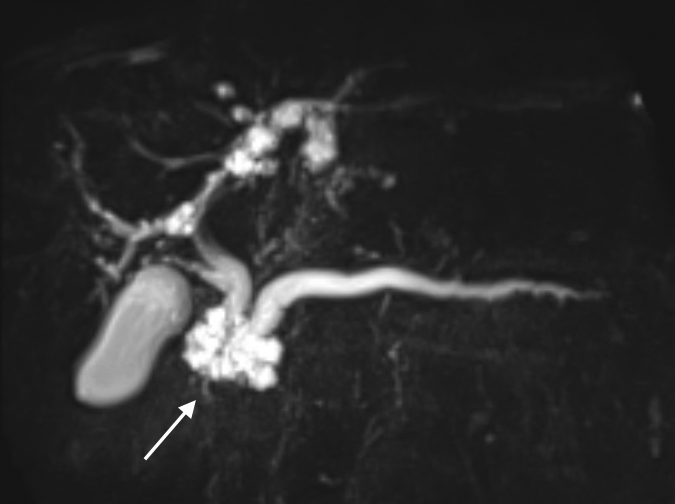

画像所見:MRCPにて膵頭部に径34 mm大の多房性の囊胞性腫瘍を認め,主膵管は径9 mmに拡張していた(Fig. 1).造影CTでも同様な所見であったが,囊胞内に隆起性成分は認められなかった.

MRCP demonstrates an IPMN 34 mm in size at the head of the pancreas (arrow). The dilated main pancreatic duct was 9 mm in diameter.